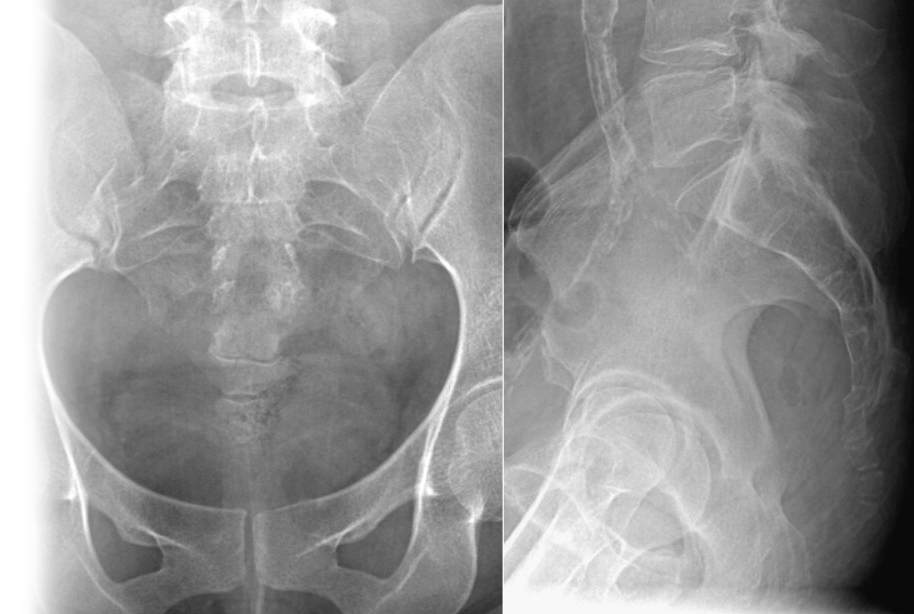

Рентгенография копчика – важный метод прицельного исследования, который позволяет оценить состояние копчика.

Диагностическая услуга выполняется в двух проекциях.